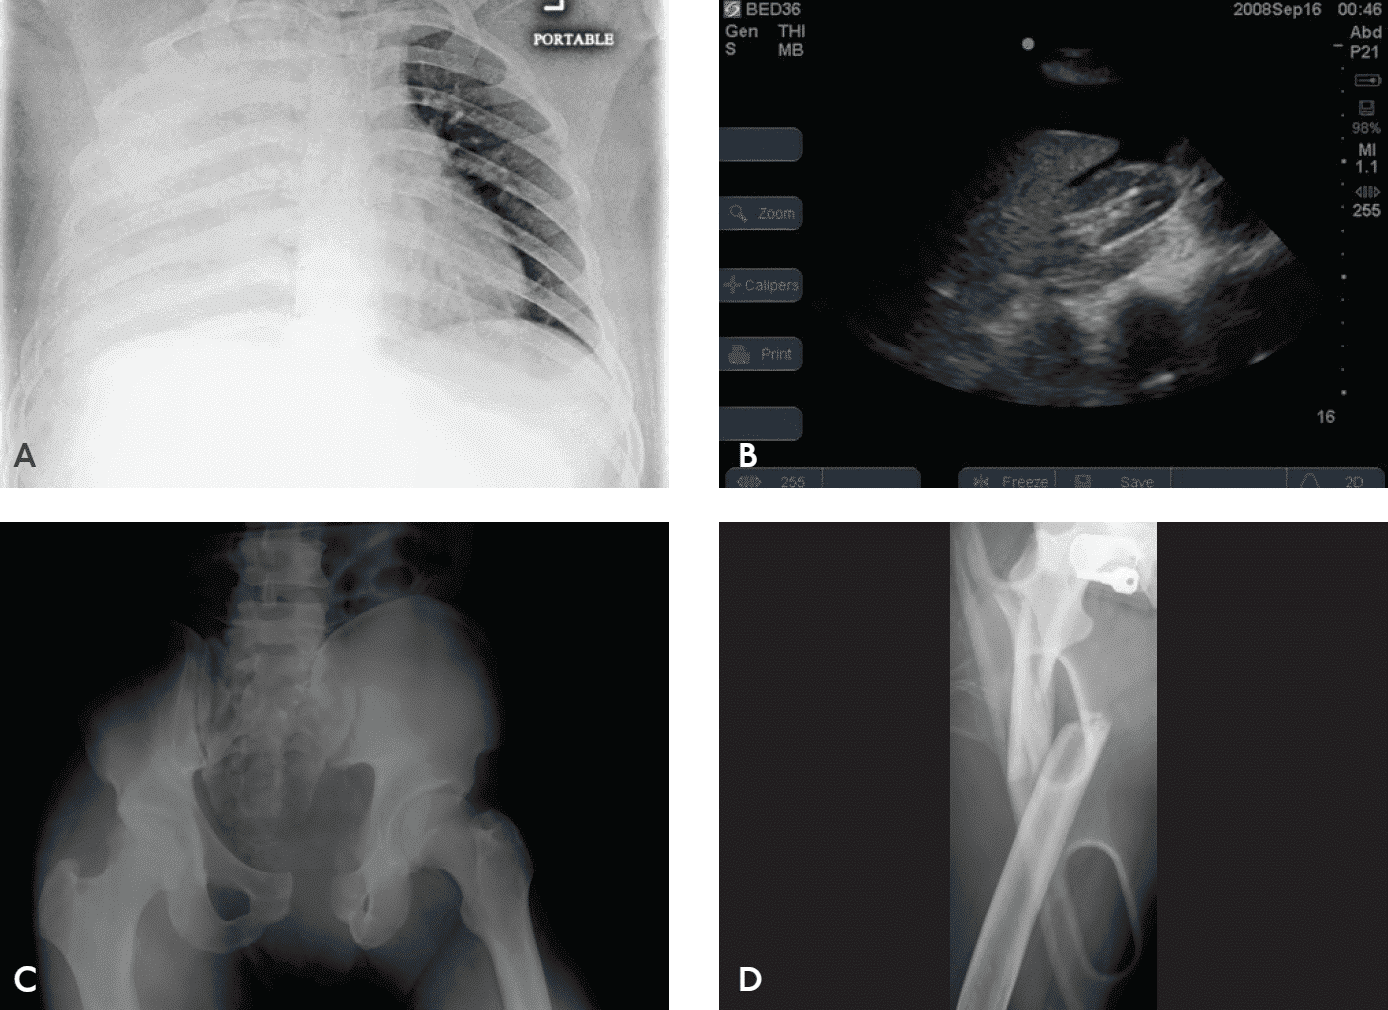

Лікування геморагічного шоку описане далі в цьому розділі, але основним завданням є рання діагностика та зупинка кровотечі. Джерела потенційної крововтрати — грудну клітку, живіт, таз, заочеревину, кінцівки, а також зовнішню кровотечу — необхідно швидко оцінити шляхом фізичного огляду та відповідних додаткових досліджень. Для визначення джерела крововтрати можуть бути корисним рентгенографія грудної клітки, рентген таза, оцінка черевної порожнини за допомогою FAST або виконання діагностичного перитонеального лаважу (ДПЛ) і катетеризація сечового міхура (Зобр. 3-2 і 3-3).

Зобр. 3-2. Використання ультразвуку (FAST) для виявлення причини шоку

Зобр. 3-3. Оцінка кровообігу включає швидке визначення джерела кровотечі. Крім поверхні, кров може бути ще в чотирьох місцях («on the floor plus four more»): A. Грудна клітка. B. Живіт. C. Таз та заочеревинний простір. D. Великі довгі кістки та мʼякі тканини.